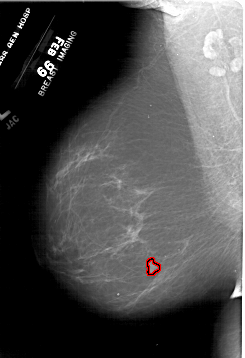

A_1848_1.LEFT_MLO

LEFT_MLO LINES 6436 PIXELS_PER_LINE 4396 BITS_PER_PIXEL 12 RESOLUTION 43.5 OVERLAY

FILE: A_1848_1.LEFT_MLO.OVERLAY

TOTAL_ABNORMALITIES 1

ABNORMALITY 1

LESION_TYPE MASS SHAPE IRREGULAR MARGINS ILL_DEFINED

ASSESSMENT 4

SUBTLETY 4

PATHOLOGY MALIGNANT

TOTAL_OUTLINES 1

BOUNDARY